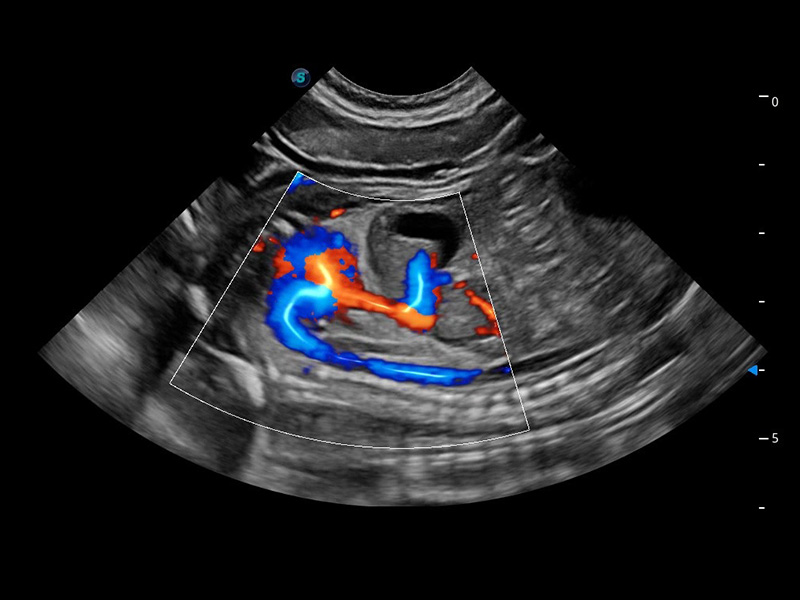

ProPet 60 作为一款高端台式动物超声设备,为动物医生的日常诊断提供了一系列贴合动物临床需求、解决临床实际问题的高级成像功能。凭借全系列高清探头,满足医生对腹部、心脏、生殖、浅表、肌骨等成像的所有需求,切实帮助您提升检查效率,提高诊断信心。

动物是人类最亲密的朋友和最值得信赖的伙伴。db真人体育官网也一直致力于探索动物专用的超声影像解决方案。 全新推出的ProPet系列,是db真人体育官网在动物超声影像智能化、专业化、精准化的一次跨越式革新。动物不能用言语来表述自己的不适,通过超声影像,ProPet系列搭建了动物医生与不同物种沟通的“桥梁”,为动物医生注入了“治愈之力”。